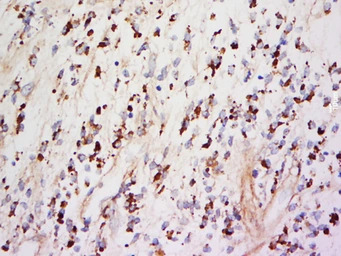

IHC-P analysis of human neurilemmoma tissue using GTX03714 TIMP1 antibody.

Antigen retireval : sodium citrate buffer (pH 6.0) boiling for 15min

Dilution : 1:500